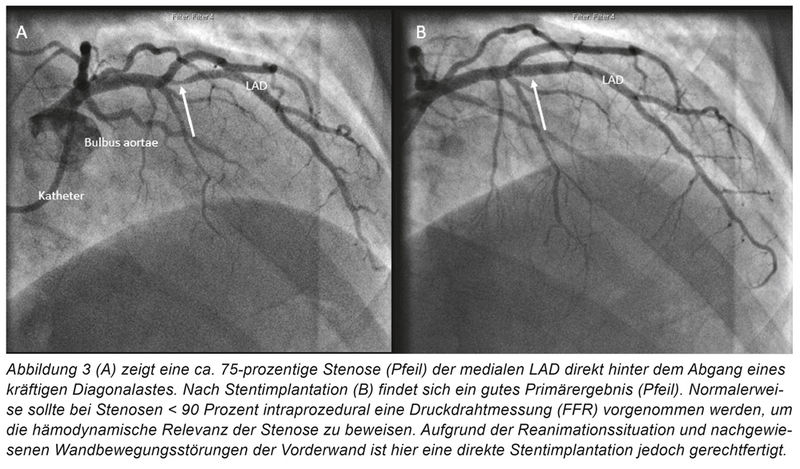

Bei anamnestisch kurz aufeinanderfolgenden Synkopen mit Verdacht auf rhythmogene Genese wird der Patient zunächst telemetrisch überwacht. Echokardiografisch zeigt sich eine mittelgradig eingeschränkte linksventrikuläre Pumpfunktion sowie eine deutliche konzentrische Hypertrophie mit angedeuteten Wandbewegungsstörungen der Vorderwand. Stunden nach der Aufnahme kommt es plötzlich zu Kammerflimmern, der Patient wird erfolgreich reanimiert. Es erfolgt eine notfallmäßige Herzkatheteruntersuchung. Hier wird eine höhergradige Stenose der medialen LAD („left anterior descending“; „Ramus interventricularis anterior“) mit einem Drug-Eluting-Stent (DES) versorgt (Abbildung 3). Zunächst könnte somit von einer häufigen Behandlungssituation im Sinne einer arrhythmogen bedingten Synkope bei Vorderwandischämie ausgegangen werden. Allerdings wird angezweifelt, ob die gezeigte Stenose tatsächlich für die polymorphen Kammertachykardien verantwortlich ist. Aufgrund dessen wird eine ergänzende kardiale MRT-Diagnostik geplant, welche eine diffuse Hypertrophie des Myokards mit früher Kontrastmittelaufnahme und einem ubiquitären punktförmigen „late enhancement“ zeigt (Abbildung 4). Auch im Verlauf kommt es wiederholt zu polymorphen Kammertachykardien woraufhin eine Aufsättigung mit Amiodaron und bei jetzt rhythmusstabiler Situation eine ICD-Implantation erfolgt. Ferner wird eine kathetergestützte Myokardbiopsie aus dem linken Ventrikel entnommen. In der initialen immunhistologischen Begutachtung zeigen sich Hinweise auf eine fokal granulomatöse Entzündung mit aktivierten Makrophagen und T-Lymphozyten, sodass jetzt von einer kardialen Sarkoidose ausgegangen und mit einer Prednisolon-Therapie begonnen wird.

Primäre Herztumoren sind insgesamt selten, das gutartige intrakavitär wachsende Myxom stellt hier gefolgt vom papillären Fibroelastom die häufigste Entität dar [9]. Zu den malignen Erkrankungen des Herzens zählt das Sarkom sowie weit häufiger eine myokardiale Metastasierung, die bei einem von fünf Patienten, welche an einem Krebsleiden versterben, im Rahmen der Obduktion gefunden wird [10]. Diese kann bei zunächst rein kardialen Symptomen unentdeckt bleiben. Im vorliegenden Fall wird erst durch das Herz-MRT der eigentliche Mechanismus für die malignen Herzrhythmusstörungen aufgezeigt. Bei ausgeprägter Hypertrophie sowie einem diffusen „late enhancement“ kommen neben einem Malignom differenzialdiagnostisch insbesondere die Sarkoidose aber auch Speichererkrankungen wie die kardiale Amyloidose, Hämochromatose oder ein Morbus Fabry in Betracht. Ferner stellt die hypertrophe Kardiomyopathie als hereditäre Erkrankung eine wichtige Differenzialdiagnose bei linksventrikulärer Hypertrophie dar. Bei progredienter Herzinsuffizienz und malignen Rhythmusstörungen ist die Myokardbiopsie zur Diagnosesicherung angezeigt. Erst durch den dramatischen Krankheitsverlauf mit Nachweis eines mesenchymalen Tumors konnte hier auch eine myokardiale Metastasierung nachgewiesen werden. Vor dem Hintergrund einer malignen Erkrankung mit in dieser Konstellation geringer Lebenserwartung (< 1 Jahr) ist im Nachhinein die ICD-Implantation kritisch zu bewerten. Diese erfolgte allerdings in Unkenntnis der metastasierenden Tumorerkrankung und infausten Prognose. Bei der koronaren Eingefäßerkrankung handelt es sich am ehesten um einen nicht relevanten „Bystander“.